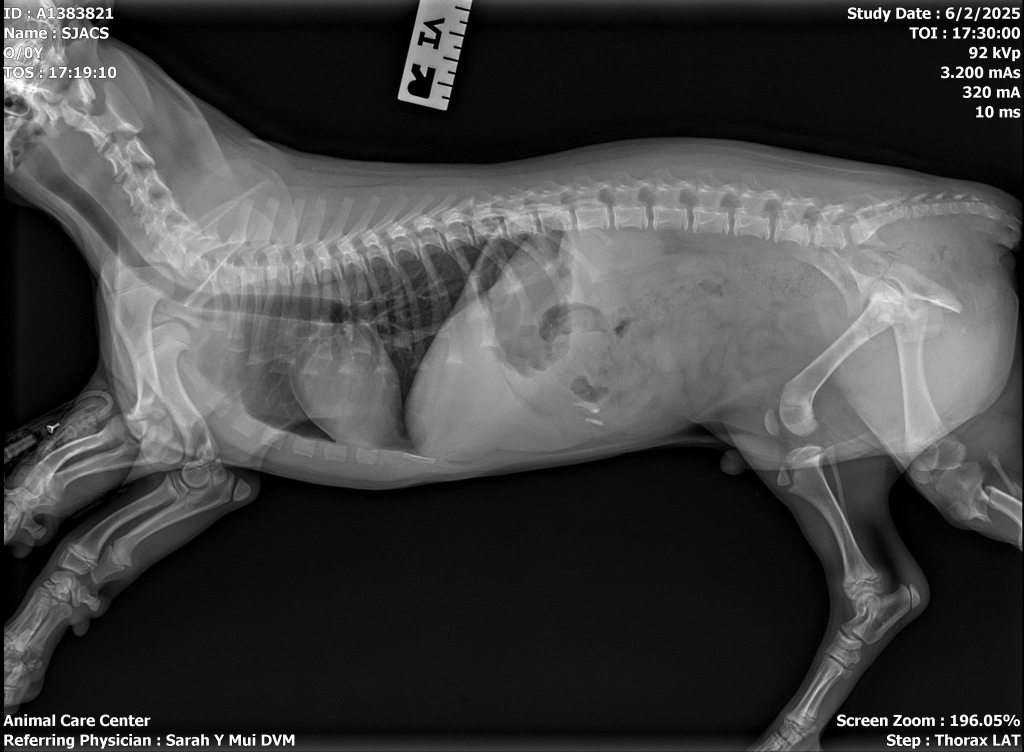

Mochi has recently been spayed, so she’s fully recovered and ready to start this new journey. Her ideal foster home would be with someone who is able to provide daily walks and continue her training, helping her develop into the well-mannered companion we know she can be.